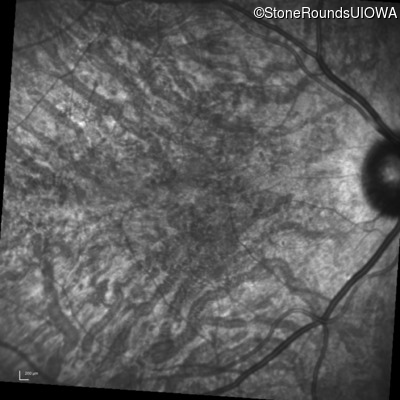

Infrared Fundus Photograph - Right - 20/40 -1

Exemplar